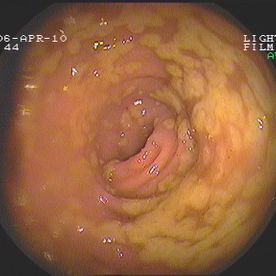

Coloskopie - Valvula Bauhini (Dünndarmklappe)